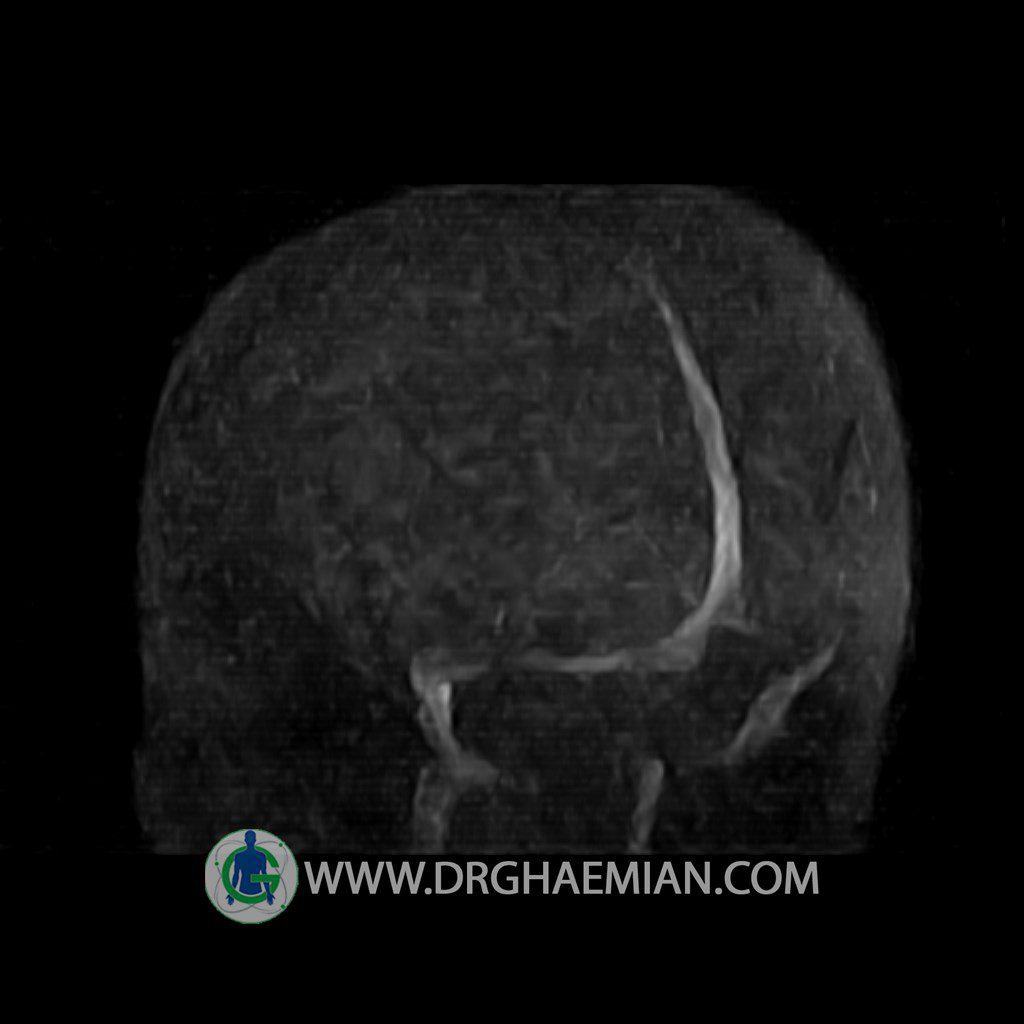

ام آر وی یک روش تصویربرداری دقیق و غیر تهاجمی است که برای معاینه ورید های بدن و ارزیابی سلامت رگ ها استفاده می شود. ورید ها خون را از اعضای بدن به قلب باز می گرداند تا دوباره اکسیژن و مواد مغذی به خون داده شود. ام آر وی جریان خون را ارزیابی و موارد غیرعادی مضر مانند لخته های خونی را شناسایی می کند. در این کیس ترومبوز دیواری مغز در سینوس عرضی راست و ترمبوز جزئی در سینوس عرضی چپ دیده می شود.

– Narrowing of left transverse sinus with filling defect & inthimal irregularity

suggestive for partial thrombosis

– Inthimal irregularity in anterior wall of right transverse sinus suggestive for mural thrombosis

are seen